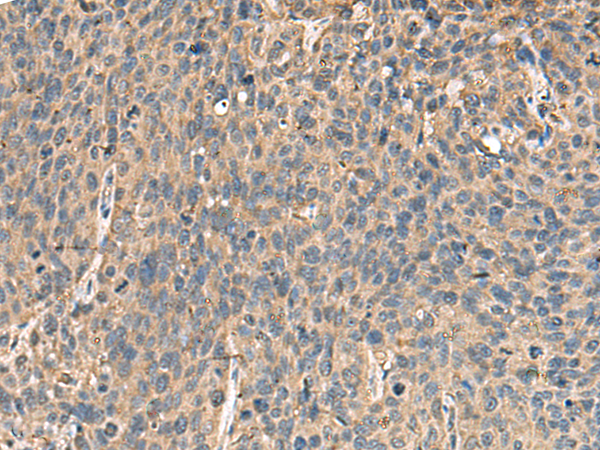

IHC positive control: |

Human cervical cancer and Human colorectal cancer |

IHC Recommend dilution: |

50-200 |